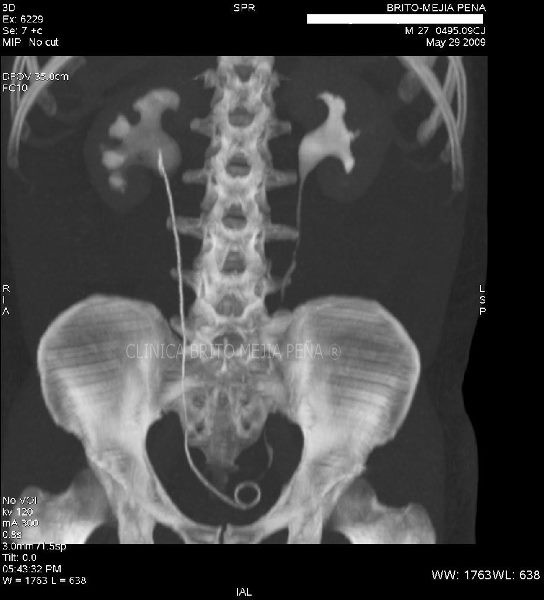

Urotac 3D

Post Image

Urotac fase excretoria